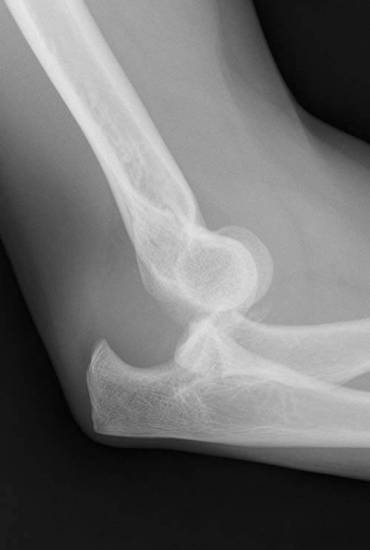

Вывих локтя с задне-боковым смещением проксимального отдела лучевой и локтевой костей (рентгенография в боковой проекции).

Вправляется вывих локтевой кости кзади вытяжением вывернутого наружу (супинированного) предплечья с одновременным выпрямлением бокового угла и разгибанием локтя. Все три последние вывиха локтя (локтевого сустава) очень редки. Точное определение их облегчается рентгеноскопией. Из изолированных вывихов локтя (локтевого сустава) гораздо большее значение имеет отдельный вывих головки луча, который возникает от прямого удара сзади наперёд или снаружи. Но он может возникать и при непрямом усилии — вследствие сильного пронирования предплечья (выкручивание руки), причём кольцеобразная связка разрывается. Чаще всего получается вывих луча вперёд и кнаружи, когда головка его лежит поверх наружного мыщелка плеча. Клинически — предплечье стоит в положении флексии и пронации и образует с плечом угол, открытый кнаружи — cubitus valgus. Головка прощупывается в локтевом сгибе — впереди или над наружным мыщелком плеча — и узнается по форме и по ротации при пронации и супинации. Задние распознавательные точки локтя не смещены. Этому вывиху локтя (локтевого сустава) нередко предшествует перелом верхней трети локтевой кости. Вправление локтя обычно легко удаётся при разгибании, вращении наружу (супинации) и вытягивании за предплечье и при прямом давлении на головку. Но с такой же лёгкостью головка снова выскакивает при движениях. Прочному удержанию её на месте препятствуют разорванные части сумки и кольцеобразной связки. Удержанию головки на месте лучше всего способствует фиксирующая повязка при вращении вовнутрь (пронировании) и сгибании предплечья под очень острым углом в локте. При невправимом вывихе локтя (локтевого сустава) препятствие приходится устранять оперативно — иногда даже резекцией головки.

Для диагностики врачам обычно хватает клинических симптомов, осмотра пациента. С целью подтверждения диагноза больному делают рентгенографию локтевого сустава в двух проекциях. Исследование позволяет визуализировать смещение, выявить сопутствующие переломы. Рентгенографию выполняют до вправления и после него.